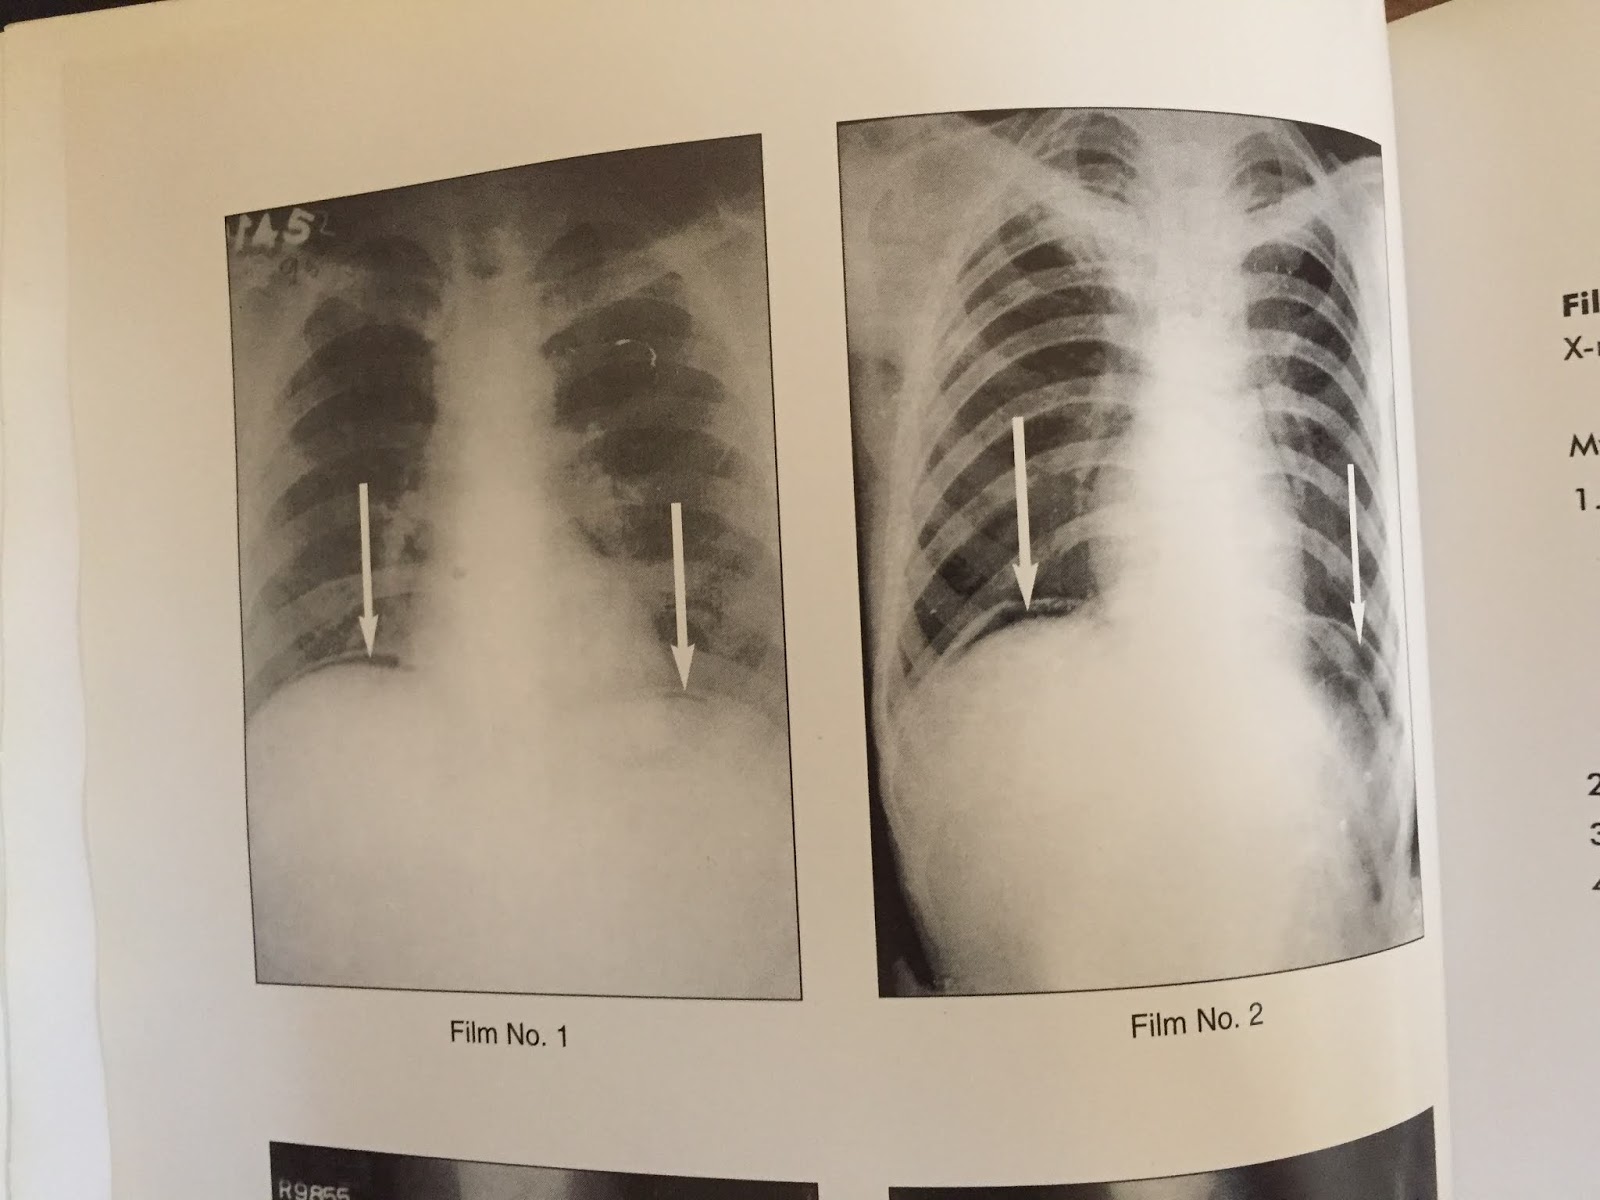

Signs of Pneumoperitoneum on Plain Film Gas Under Diaphragm Sign Name The stomach bubble forms a round/ovoid shape under the left hemidiaphragm. Haustra within the gas suggesting that it is within the. Gas between liver and diaphragm. As the stomach has a thick wall, there is a thick line separating gas in the stomach from air in the lungs. Features that suggest chilaiditi sign include: Pneumoperitoneum (aeroperitoneum is a rare synonym. Gas Under Diaphragm Sign Name.

Gas Under Diaphragm Final Year MB BS Lecture Gas Under Diaphragm Sign Name Haustra within the gas suggesting that it is within the. The stomach bubble forms a round/ovoid shape under the left hemidiaphragm. Pneumoperitoneum (aeroperitoneum is a rare synonym 12) describes gas within the peritoneal cavity, often due to critical illness. Features that suggest chilaiditi sign include: As the stomach has a thick wall, there is a thick line separating gas in. Gas Under Diaphragm Sign Name.